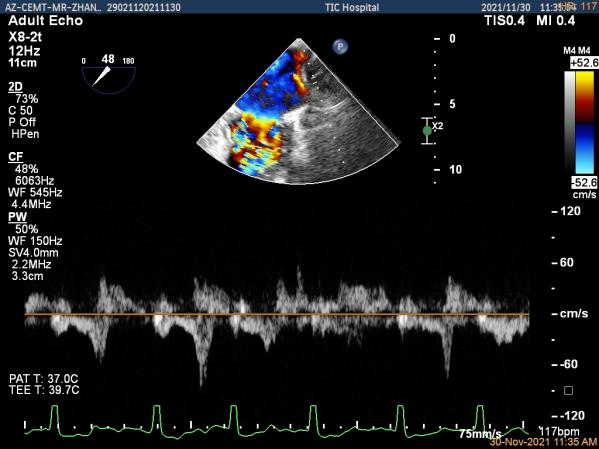

术前超声评估结果

术前超声诊断

Qlab软件勾画估测瓣口面积约:4.42cm²

二尖瓣口平均跨瓣压差:5mmHg